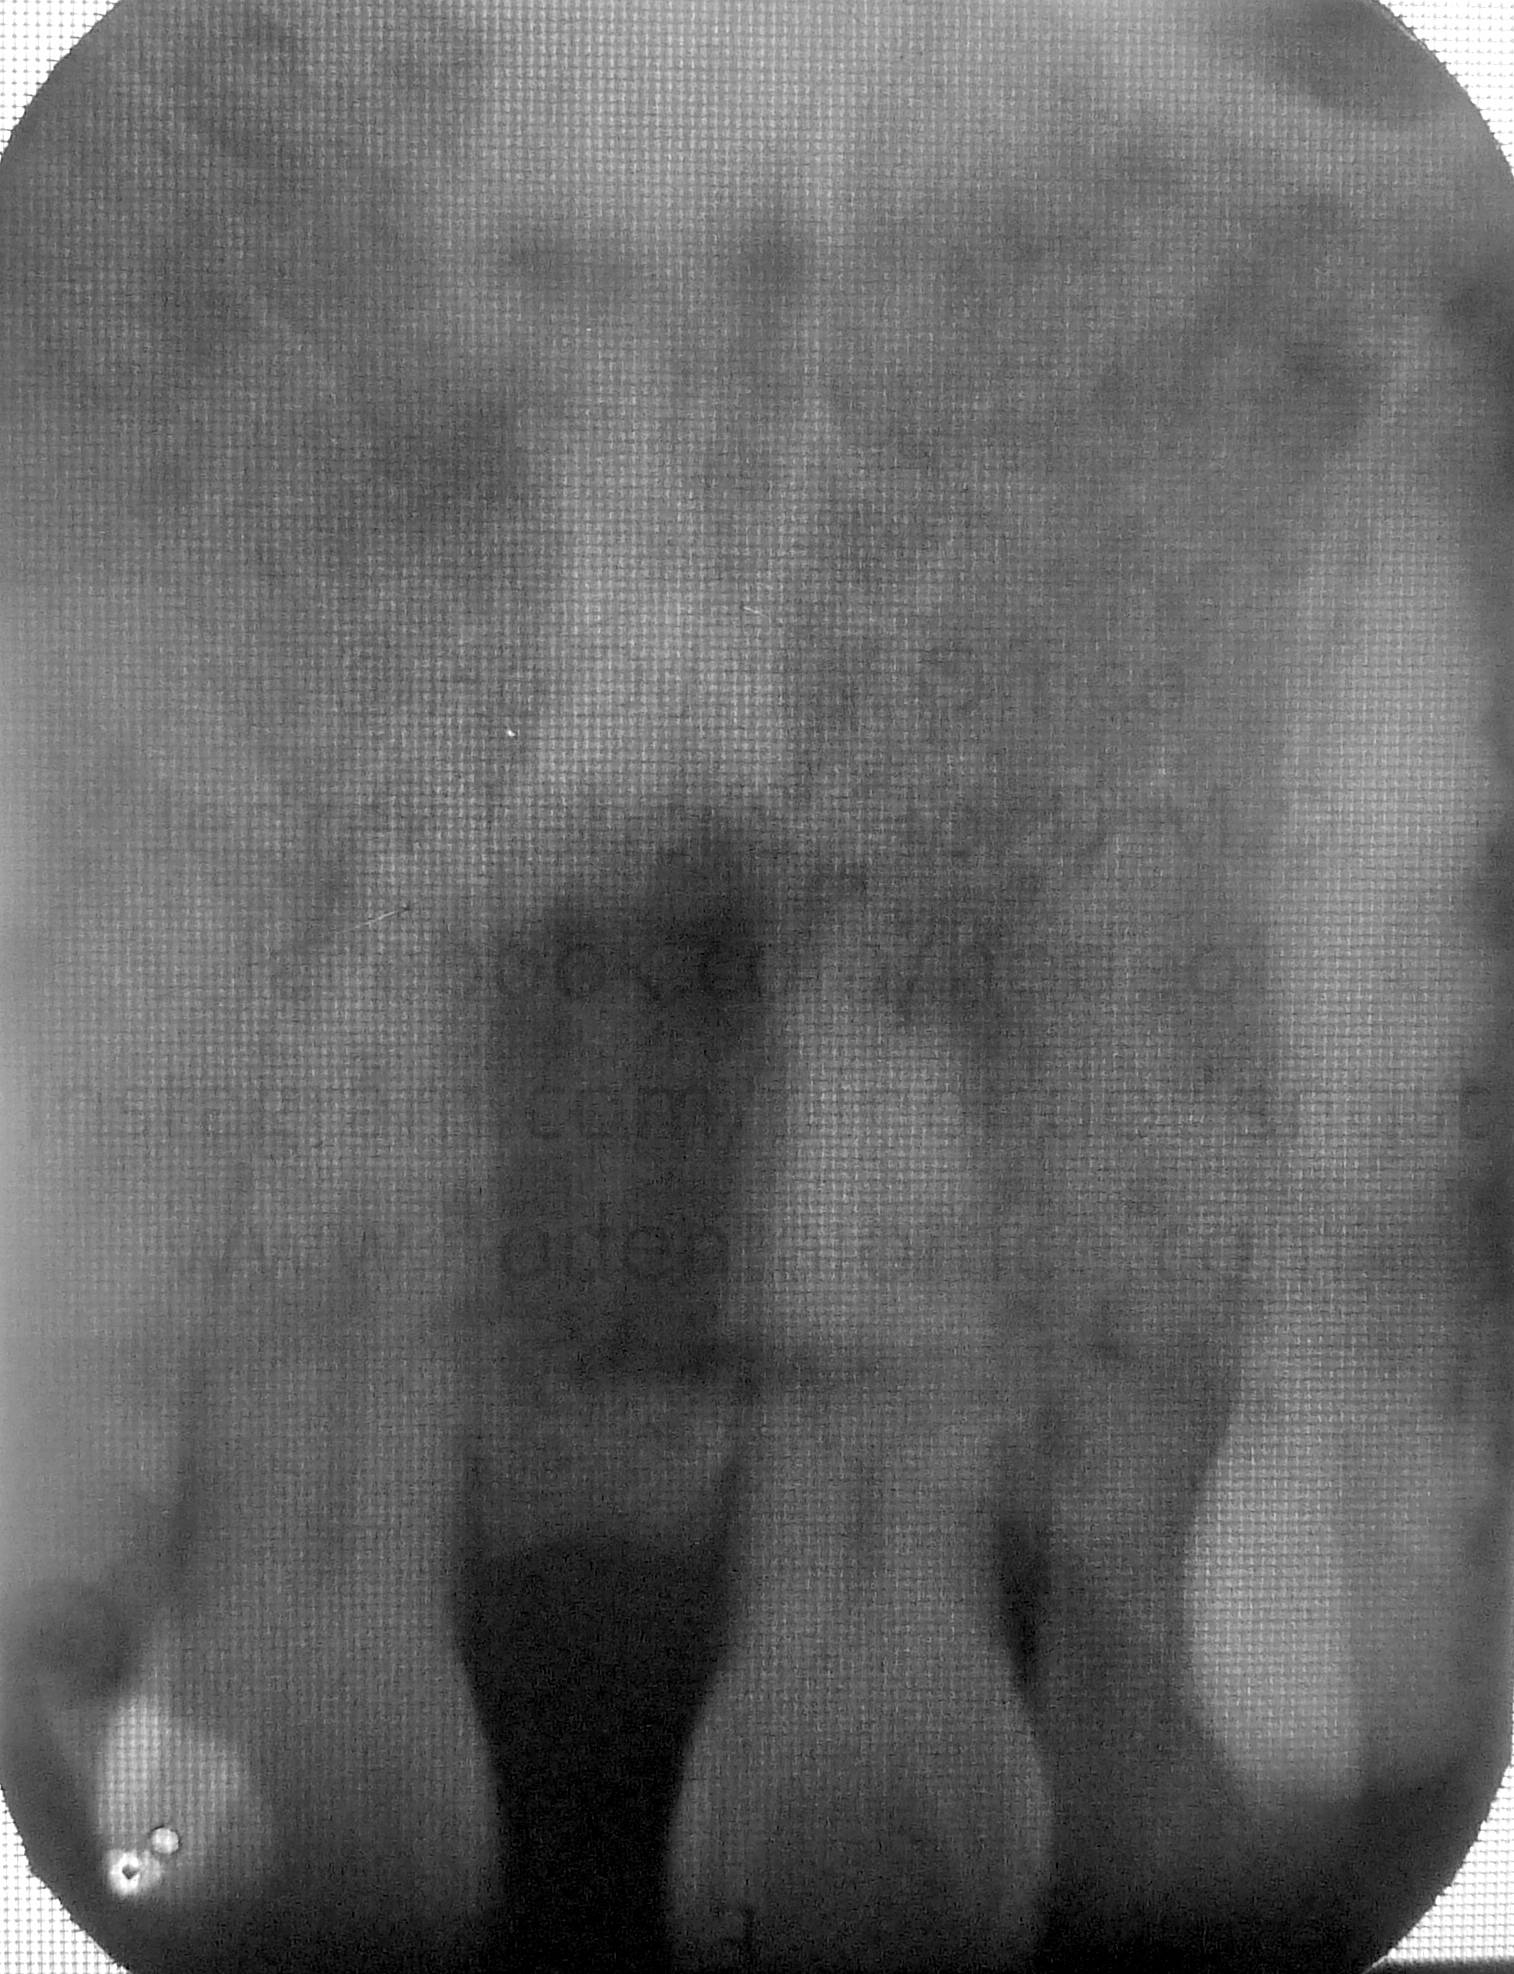

Upon observation, a very big frenum attachment is evident, with the "pull" of the muscle fibers (seen while stretching the lips) reaching all the way up to the incisive papilla on the back of the upper incisors. Patient was also checked with x-ray to ascertain presence of impacted teeth, if any.

X-ray results shows no signs of impacted teeth in between the two incisors. This area is common to having an impacted "mesiodens" - a supernumerary (extra) tooth - literally meaning a "tooth in the middle".

Since the cause of the diastema (big gap in the middle) was determined to be not caused by a hidden impacted tooth, it is highly likely that the strong frenum muscle attachment was the one causing it, as there have been documented cases similar to this that can be seen on dental textbooks and scientific papers.